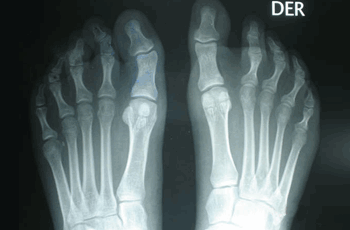

RESULTADOS

Caso 2: Hallux Valgus del Adolescente

Pie Izquierdo operado